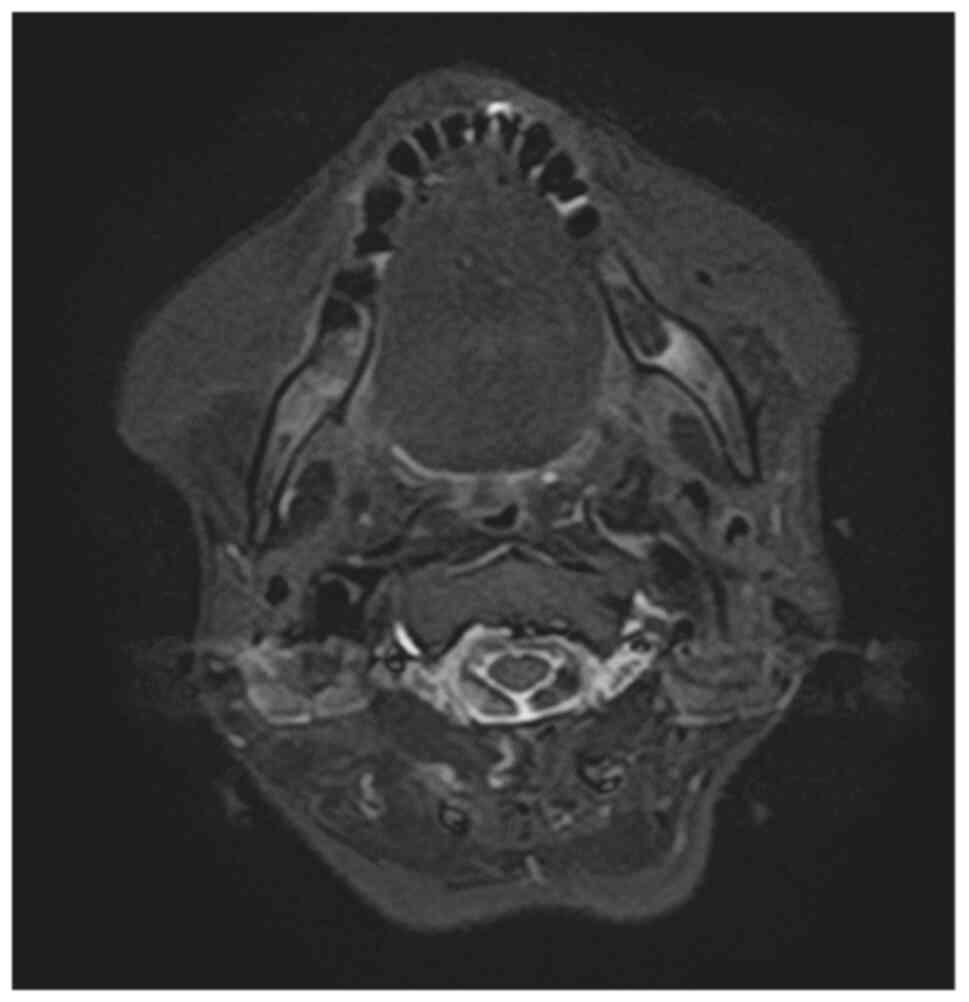

Methotrexate‑related other iatrogenic immunodeficiency‑associated lymphoproliferative disorder (MTX‑OIIA‑LPD) is prone to extranodal involvement but rarely involves the central nervous system (CNS). The present study reports a case of MTX‑OIIA‑LPD of the CNS discovered during medication‑related osteonecrosis of the jaw (MRONJ) treatment in a 76‑year‑old woman with rheumatoid arthritis (RA). The chief complaint of the patient was bone exposure and pain in the right mandibular molar. The patient had been receiving MTX for RA and alendronate sodium hydrate for osteoporosis, followed by denosumab. Treatment was initiated based on a diagnosis of MRONJ. However, the patient experienced lightheadedness and floating dizziness afterwards. Examinations revealed scattered neoplastic lesions in the brain. The histopathological diagnosis was diffuse large B‑cell lymphoma. A systemic search also revealed adrenal involvement. Since the patient was taking MTX, a diagnosis of MTX‑OIIA‑LPD was made and MTX was discontinued. Chemotherapeutic agents were administered since the central lesions became symptomatic. The MTX‑OIIA‑LPD lesions in the brain and adrenal glands completely resolved 8 months after onset. The physical condition of the patient improved, and the bone‑exposed areas became epithelialized. Reports on MTX‑LPD in the oral and maxillofacial region are few, which may delay its diagnosis. Therefore, biopsy of oral lesions in patients with MRONJ who are taking MTX and collaboration with related diagnostic departments, such as rheumatology and hematology, must be done to initiate the diagnosis and treatment of extraoral MTX‑LPD.